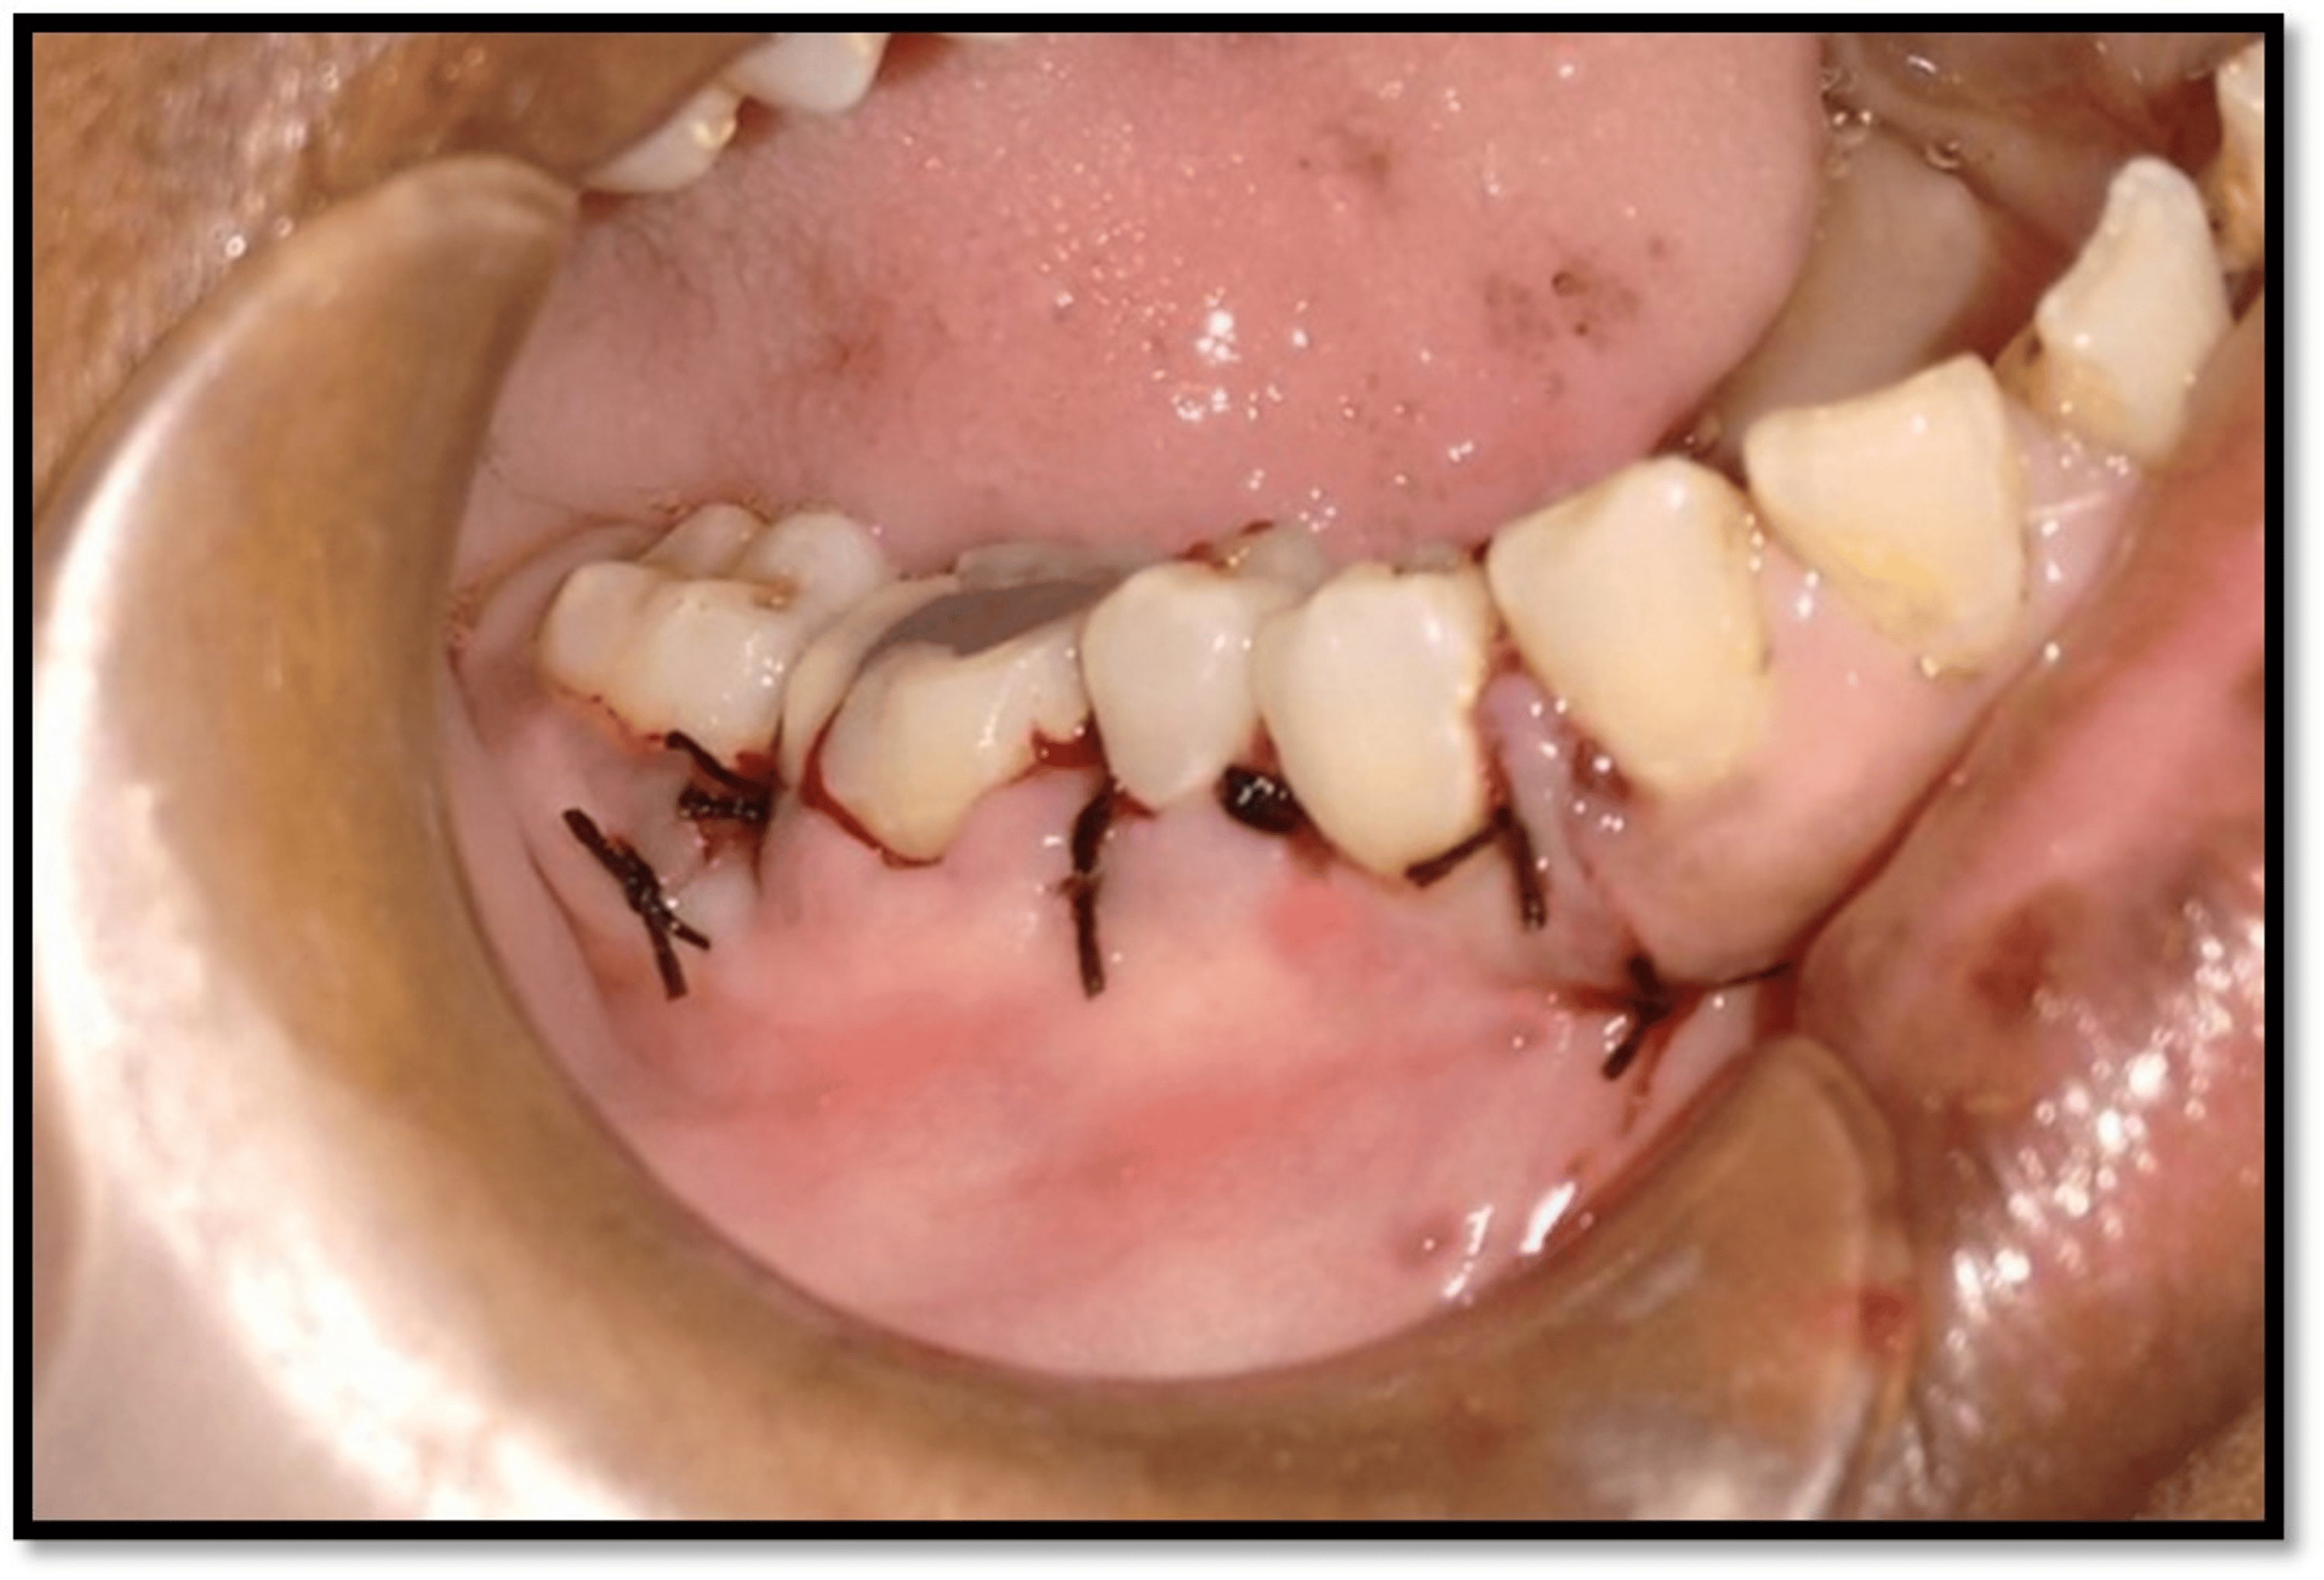

Tooth Extraction Bone Graft Sutures . Get all of your questions answered on realself. It varies, typically taking several months for the graft to fuse with your natural bone. But for the bone graft to fully integrate into your jawbone, it goes through a longer process. The graft material is placed where bone is needed. After your dental bone graft, follow your dentist’s aftercare instructions meticulously. After tooth extraction and socket bone grafting. Brush your teeth and avoid. Tooth extraction is a surgical procedure. These instructions apply for surgical treatments that include both tooth extraction and the placement of grafting material in the extraction site. It is natural that changes will occur. When having a bone graft, your gums heal quickly, usually within the first week. The incision is sutured closed to heal naturally. A key thing to know.